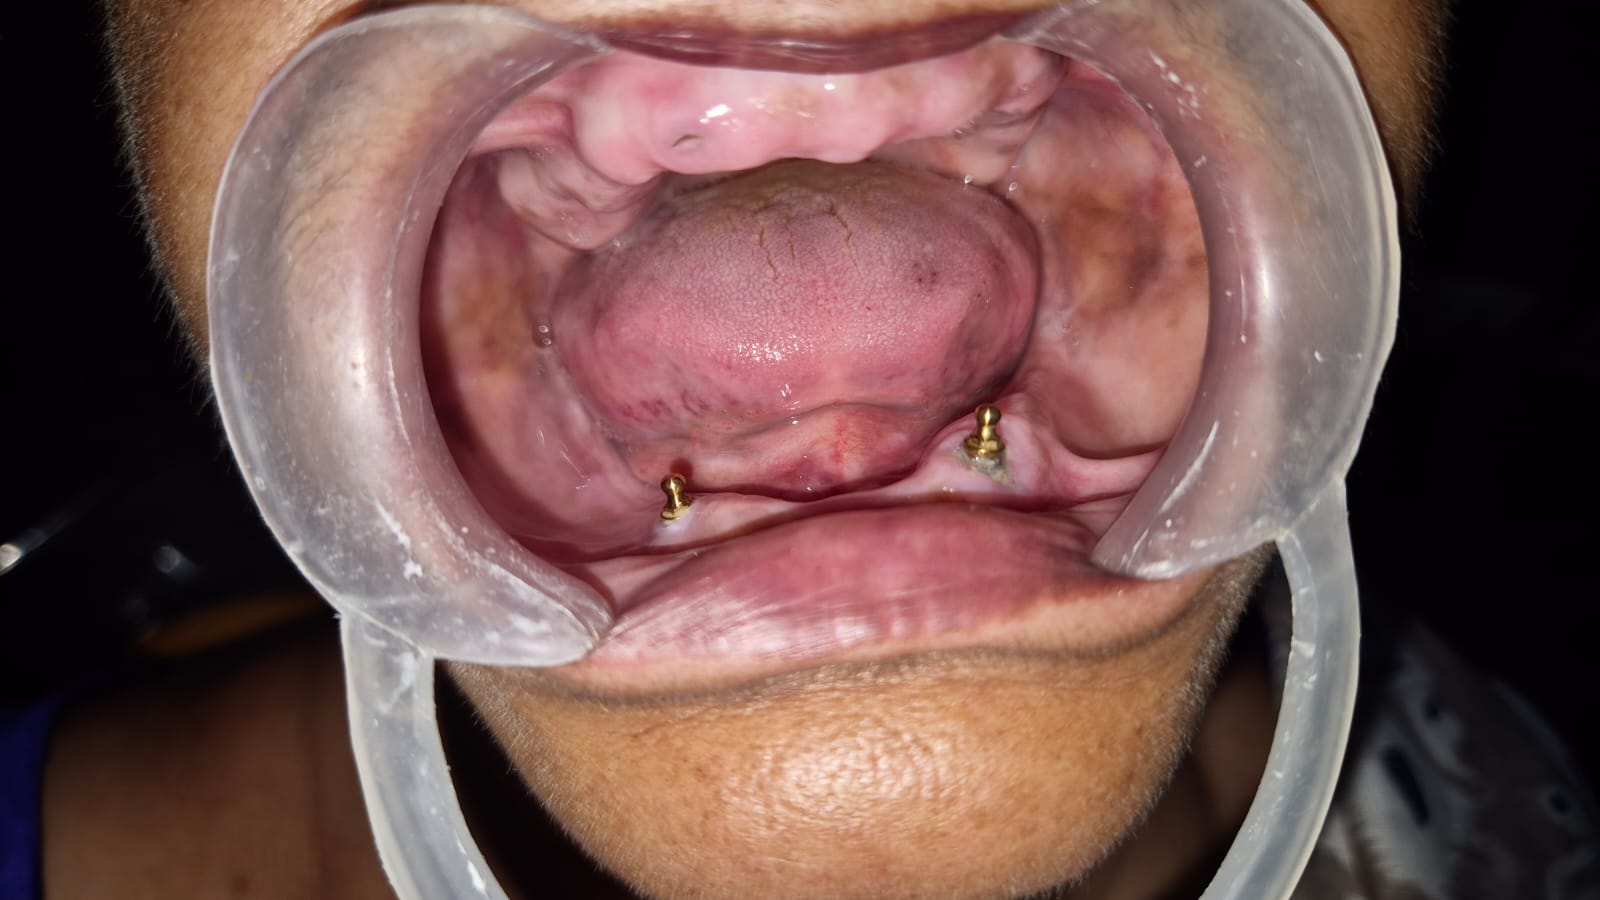

Restore your smile with advanced implantology at Teeth Care Multispeciality Dental Clinic in Kolkata. Our expert implant specialists provide personalized solutions, including All-on-4, All-on-6, full-mouth, and single tooth implants. Using modern technology and precise techniques, we ensure durable, natural-looking results. Experience comfortable, long-lasting dental restoration that enhances both function and confidence.

- All-on-4 Implants are designed to replace a full arch of teeth using just four implants strategically placed in the jaw. This approach is ideal for patients with significant tooth loss or moderate bone density, minimizing surgical intervention and recovery time while offering excellent stability.

- All-on-6 Implants involve six implants per jaw, providing enhanced support and strength for full-arch restorations. This solution is recommended for patients with sufficient bone structure who desire superior stability and a natural-feeling full smile.

- Full-Mouth Implants are a comprehensive solution for patients who have lost most or all of their teeth. By combining multiple implant techniques, including All-on-4 or All-on-6, our specialists restore both the upper and lower jaws. Full-mouth implantology offers a permanent, functional, and aesthetically pleasing outcome for extensive tooth loss.